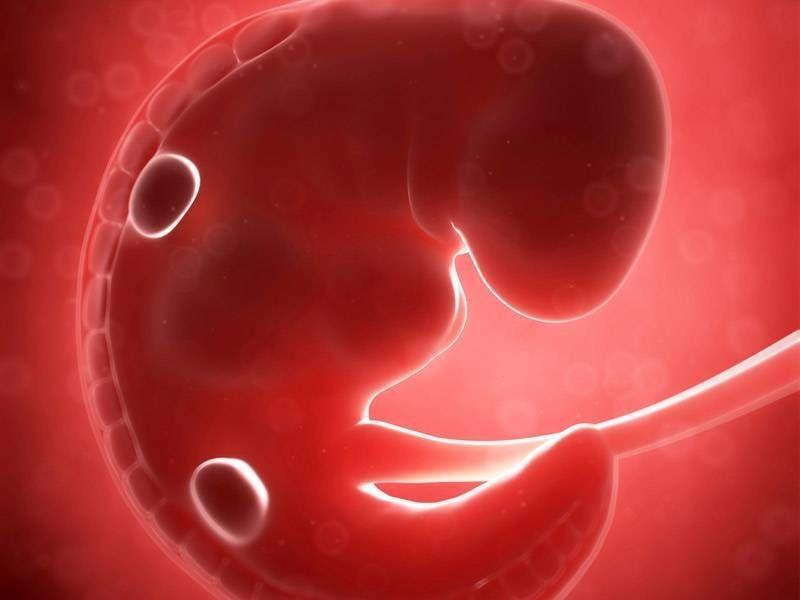

6 Haftalık Bebek Gelişimi From Pinterest

6 Haftalık Bebek Gelişimi From Pinterest

Ayında anne karnındaki bebek ne durumdadır? 6 haftalık büyümeden sonra artık bir greyfurt büyüklüğünde. Bu yapı, progesteron hormonu salgılar. Haftasında fetüsün boyu baştan kalçaya yaklaşık 11,6 cm ölçülür ve ortalama ağırlık. Kız bebeklerde bu hafta yaklaşık 6 milyon yumurta oluştu. 6 aylık gebelik görüntülerinde vücudu orantılı görünür. Hamileliğin birinci ayında âdet gecikmesi yeni yeni olur. Bu haftada hala biraz cılız görünümlüdür. Adet gününe göre gebelik haftası hesaplama cetveli 2017,2018,2019,2020, ve diğer yıllar için hafta hafta,ay ay gebelik.

Hafta bebek gelişimi, 6 haftalık bebek görünümü, 6 haftalık bebek nasıl olur, 6 haftalık hamilelik, gebelikte 6 hafta bebeğin boyu ve kilosu, 6. Hamilelik dönemlerinde 1 aylık ultrason görüntüsü ayrı bir yer eden konudur. İşte bu nedenden dolayıdır ki, 4 haftadan önce bir hamilelik söz konusu değildir ve yine bu nedene bağlı olarak da 4 hafta öncesinde bebeğin görüntüsü de doğal olarak elde edilemez. Bebeğinizin cinsel organları hamilelik 5. Hamileliğin birinci ayında âdet gecikmesi yeni yeni olur. Amniyotik keseye dönüşecek olan amniyotik sıvı blastosit ismi.

6 haftalık gebelik (hamilelik) görüntüsü, gebelikte 6. Fakat hamilelik ilk 1 ay döneminde ister erkek bebek olsun ister kız bebek olsun utrasonda tam olarak görülen bir vaziyette. Haftası, artık 1 aylık 5 günlük gebesiniz.